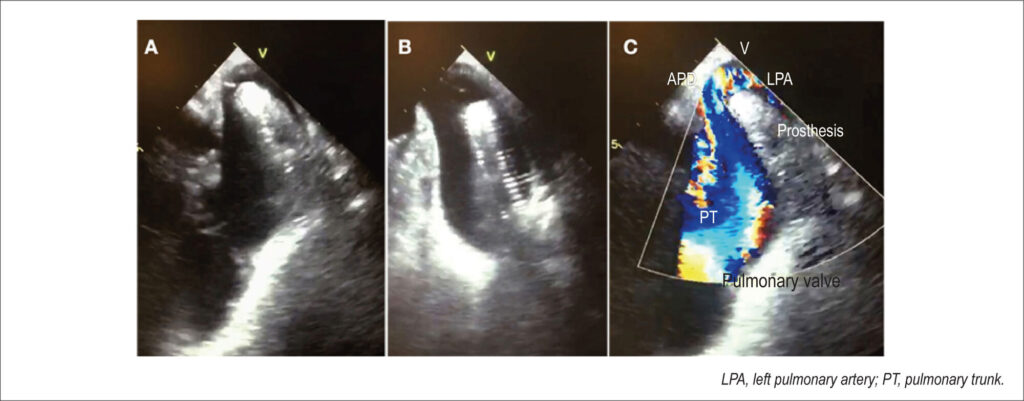

Figura 1

Imagens do ecocardiograma transesofágico mostrando prótese Amplatzer™ deslocada para tronco de artéria pulmonar (A e B). Doppler colorido mostrando fluxo turbilhonado no tronco da artéria pulmonar (C).